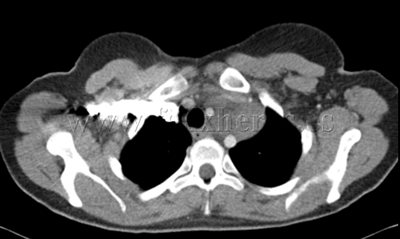

Linfoma cérvico-mediastínico

Biopsia por videomediastinoscopia